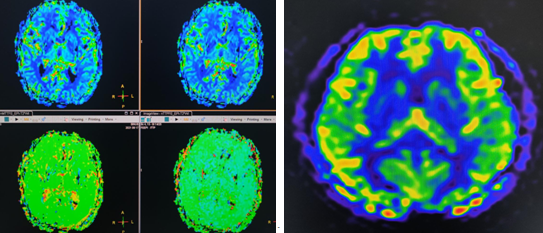

2.脑肿瘤、脑外伤,脑发育畸形,感染性疾病等,同时可进行磁共振弥散加权成像(DWI)、磁共振弥散张量成像(DTI)、磁共振波谱成像(MRS)、血氧水平依赖成像(BOLD)、磁共振灌注成像(PWI),动脉自旋标记成像(ASL)、磁敏感加权成像(SWI)等多种功能成像。

磁共振弥散张量成像(DTI) 磁共振波谱成像(MRS)

磁共振灌注成像(PWI) 动脉自旋标记成像(ASL)